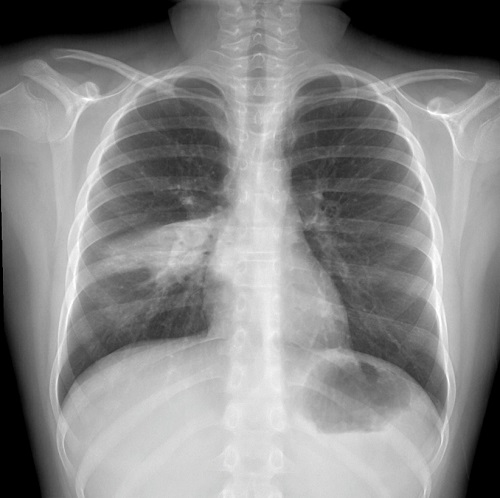

A las 48 horas acuden a urgencias hospitalarias por tos de predominio nocturno que le impide conciliar el sueño. En urgencias hospitalarias la auscultación cardiopulmonar (ACP) es anodina. Se le realiza analítica sanguínea, en la que destacan leucocitos totales 11,28 x 109/l y hemoglobina (Hb): 13,9 g/dl. En la radiografía de tórax (Rx tórax) se evidencia una neumonía en el lóbulo medio derecho, por lo que se inicia tratamiento con amoxicilina oral (Figura 1).

Figura 1. Radiografía del tórax con infiltrado en lóbulo medio derecho sin derrame asociado